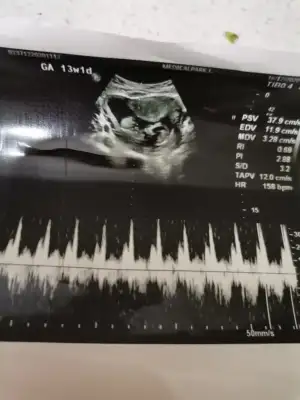

Canım 16. Haftadan önce kesin söylüyolarmı cinsiyeti? Bende 16. Haftayı bekliyorum öğrenmek içinBu gün tam 13+1 günlük olduk geçen hafta doktor kız gibi dedi emin değilim dedi ama bu gün kız dedi

Kız gibi emin olamadım başka USG varsa paylaşın 11 12 13 haftalar olmalı

Şimdilik erkek yönünde en iyi nub için 11 12 13 haftalar olmalı tekrar paylaşın

Banada bakarmısınız bu gün doktor kız dedi yüzde doksan dediEn iyi 11 12 13 haftalar olmalı

Kız görünüyorBanada bakarmısınız bu gün doktor kız dedi yüzde doksan dedi